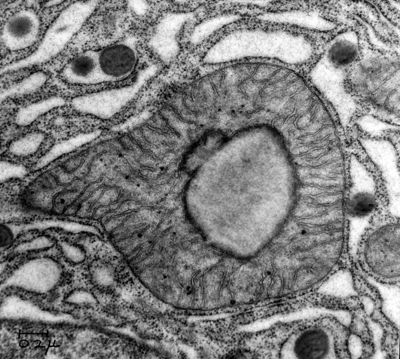

One of the first nanoartists in the history, probably without his intention to create art was George Emil Palade (1912 - 2008), a Romanian cell biologist. Described as "the most influential cell biologist ever" (Hopkins, 2008), he was awarded in 1974 the Nobel Prize in Physiology and Medicine together with Albert Claude and Christian de Duve for innovations in electron microscopy and discoveries concerning the structural and functional organization of the cell that laid the foundations of modern molecular cell biology. The most notable discovery was the ribosomes of the endoplasmic reticulum

described by Palade first in 1955.

| Palade, George E. - Mitochondria Guniea Pig Pancreas lipid droplet |

The collection of images includes some of the earliest electron micrographs taken by George Palade and his collaborators at the Rockefeller University (1945-1973) and at Yale University (1973-1990). Electron micrographs taken by Marilyn Farquhar (the glomerular basement membrane in renal filtration), Maya and Nicolae Simeonescu (capillary endothelium), James Jamieson (secretory pathway in the exocrine pancreas; atrial granules), Lucien Caro (electron microscopic autoradiography), Philip Siekevitz, John Bergeron and Japoco Meldolesi (microsomes, Golgi fractions), and Sanford Palay (synapses) are part of the collection.